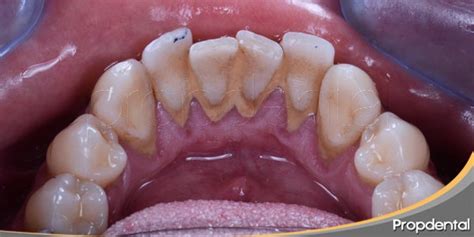

También conocido como cálculo dental, el sarro es una acumulación de placa bacteriana junto con saliva y restos de alimentos que se va depositando en los dientes y se va endureciendo. Tiene un color amarillento, cuando se sitúa por encima de la línea de la encía, o marrón, cuando se deposita por debajo.

Primero, trataremos la tartrectomía supragingival que es el procedimiento utilizado para retirar los cálculos acumulados por encima de la línea de la encía. Para ello, se lleva a cabo un raspado coronal y una limpieza bucal rutinaria para eliminar la placa y algunas manchas en los dientes.

Segundo, la tartrectomía subgingival, por su parte, se utiliza para eliminar los cálculos acumulados por debajo de la línea de las encías. En este caso, se realiza un raspado radicular para eliminar los cálculos que se acumulan entre los dientes y las encías.